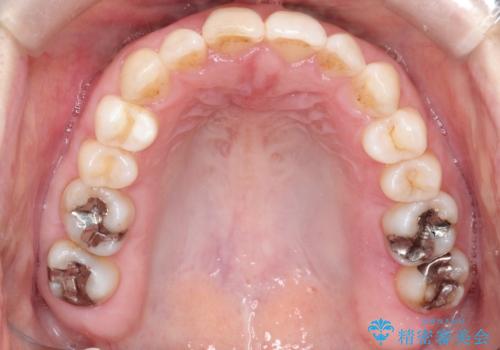

【インビザライン 】前歯のガタガタを治したい

- 前歯のガタガタを主訴に来院されました。

インビザライン で治療しました。途中は使用時間が20時間を切ることもありましたが、それでも頑張って使っていただき1年半で矯正終了することができました。